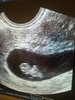

Witam. Ja dziś po wizycie. Oczywiście skierowanie do diabetologa. Moja fasolinka rozwija się prawidłowo, serduszko wali *:0)Krwiak nadal jest. Nie jest duży. Doktor nie kazał się nim przejmować.,twierdzac że się wchlonie.Mam taka nadzieje...

A to sefliczek dzisiejszy mojej fasoli *:0)

Załączniki

• IMG_20180717_154712.jpg

IMG_20180717_154712.jpg

1,6 MB · Wyświetleń: 104